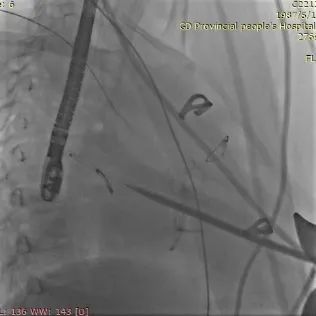

TEE&DSA引导下进入加硬导丝建立轨道

DSA&TEE引导下J-Valve定位件展开,瓣膜自膨后形态、位置良好

球囊后扩;舒张期J-Valve瓣膜前向血流通畅;收缩期未见明显瓣周漏